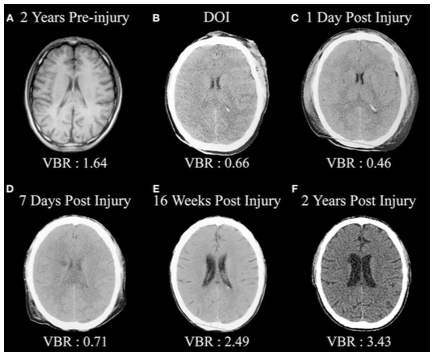

On the macro level, Bigler (2013) demonstrated these neurodegenerative changes over time via sequential MRI imaging in a patient with moderate TBI. (6) (Figure 3). Other studies indicate an increased risk of depression over time. (8,9)

Following mTBI, individuals often experience symptoms of post-concussive syndrome (PCS). PCS symptoms include headache, dizziness, sleep disturbance, personality change, memory problems, attention and affective disturbances. 90% of mTBI PCS symptoms resolve completely. The 10% or so of patients with mTBI whose symptoms do not resolve within three to six months, develop persistent post-concussive syndrome (PPCS). (Fig 1)